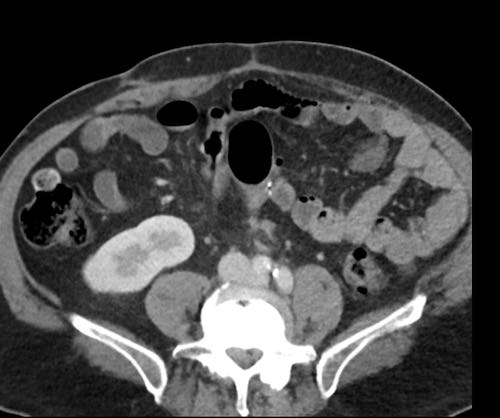

Cuộn xem ảnh CT

Ca lâm sàng 1

Cuộn qua các lát cắt.

Bạn có thể phát hiện tất cả các tổn thương cấy ghép phúc mạc không?

Bệnh nhân này đã được phẫu thuật và toàn bộ phúc mạc được ghi nhận phủ kín bởi các tổn thương u dạng kê.